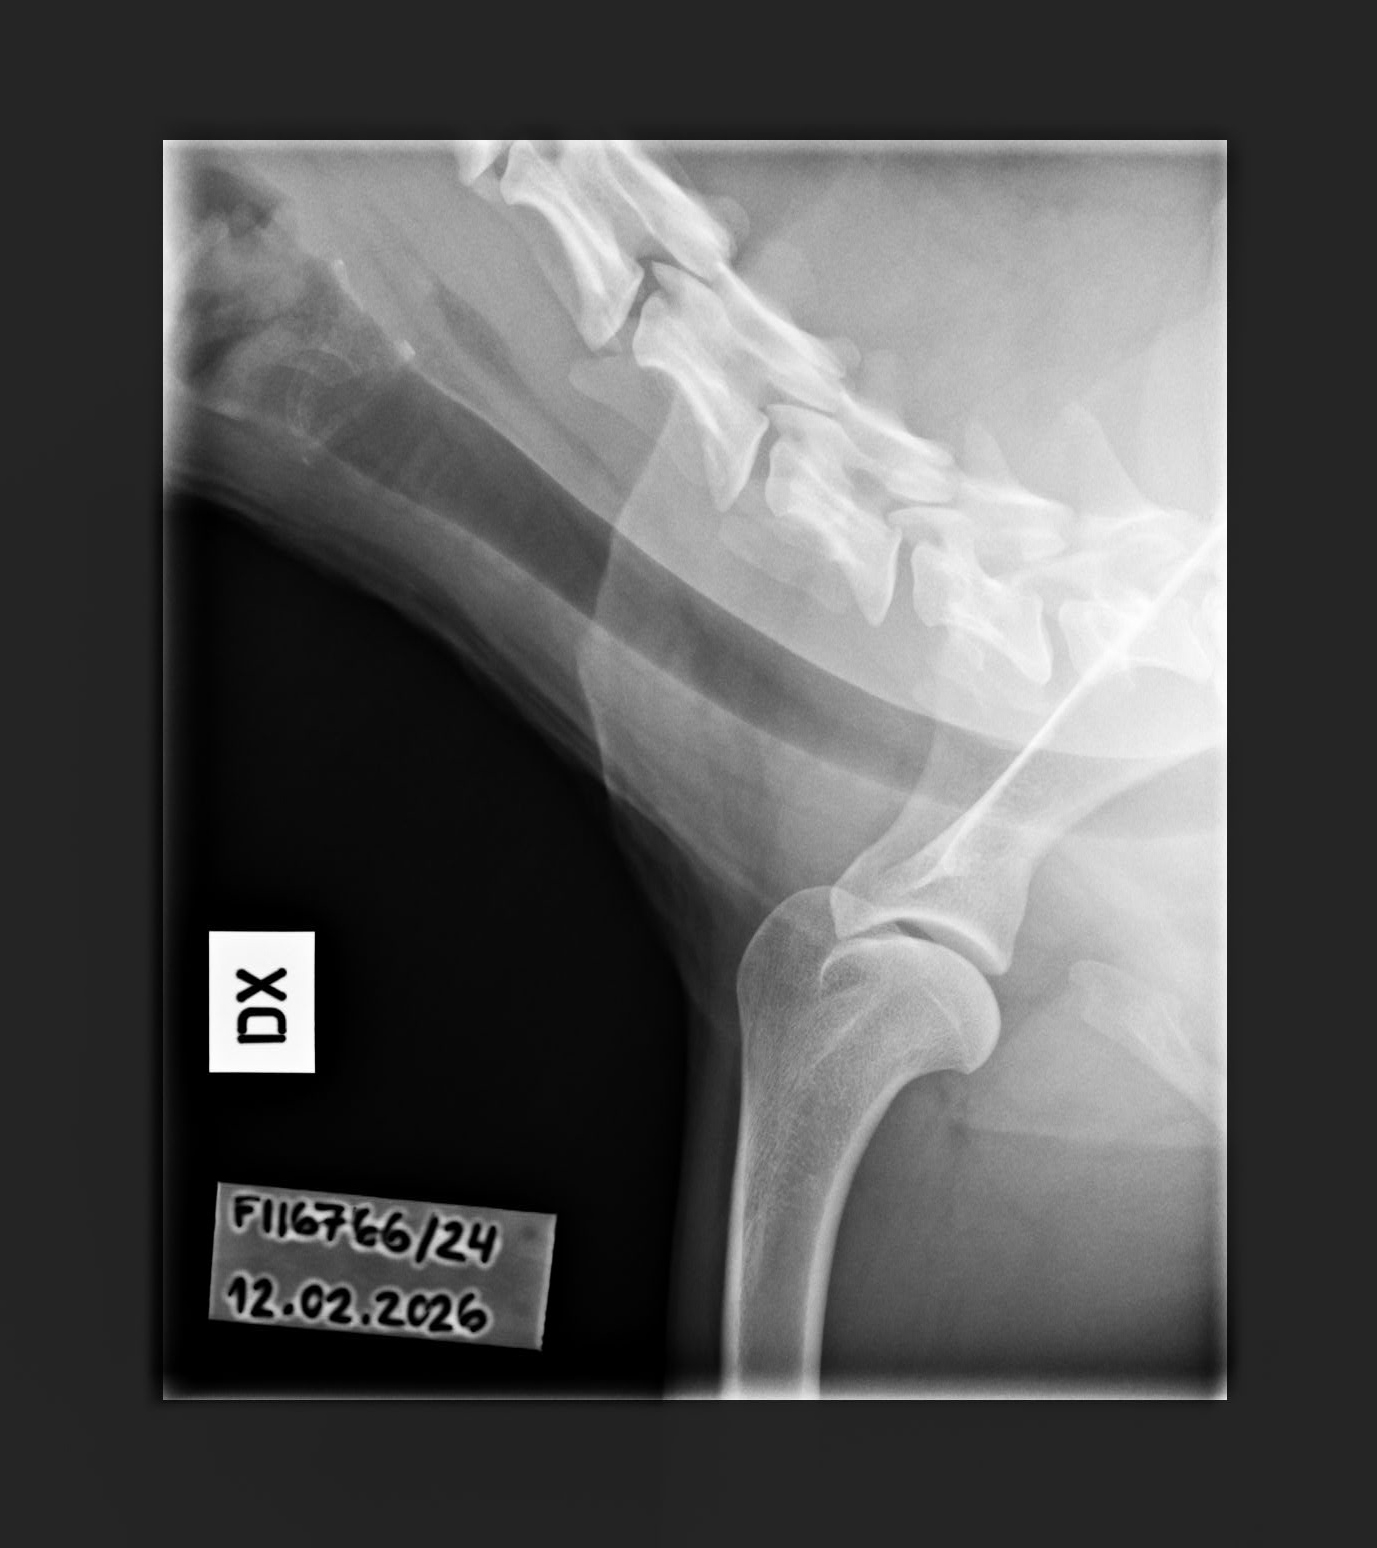

NHAT Pihlajamäen Aslan ♂ Personal

C/B |

1/0 (see Notes) |

- Finnish Kennel Club's elbow x-ray report Dec '25: Signs suggestive of medial coronoid disease; further information about the condition of the joints can be obtained, if necessary, by computed tomography (CT) examination

- Finnish Kennel Club's elbow CT report Feb '26: A small amount of new bone formation around the medial coronoid process of the left elbow

- Shoulder osteochondritis: Unaffected/Unaffected

- Free of lumbosacral transitional vertebrae (LTV0)

- Free of spondylosis (SP0)

- Spine x-rays: 1, 2 ja 3